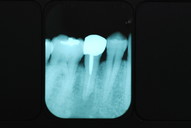

必ずばい菌が侵入しないようにしてばい菌である虫歯を除去します。

銀歯の下はばい菌だらけです。こういうのはよくあります。取り残しですね。![treatment_05[1]](https://livedoor.blogimg.jp/netdental/imgs/3/a/3ad019d0-s.jpg)